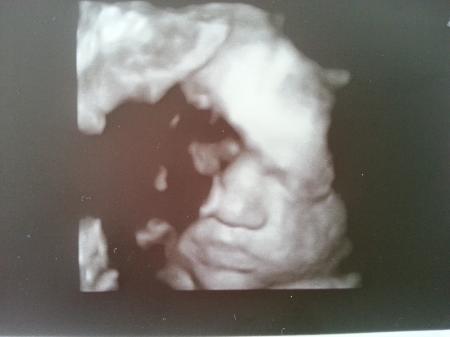

Hier noch das Bild von gestern! Sie hält sich das Händchen vors rechte Auge, die klein Diva

Bild zu